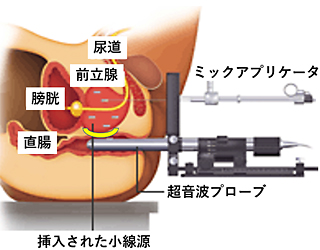

密封小線源療法とは何ですか?

小さな線源を前立腺内に挿入し、前立腺内のがん病巣へ線源から放射線を照射する放射線治療です。